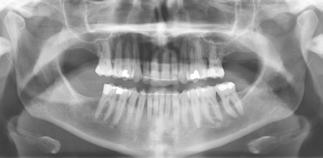

PATIENTTILFÆLDE 1

Patienttilfælde 1 (Fig. 1) er en 37-årig kvinde, henvist efter succesfuld behandling af stadie 3-parodontitis. Der er nu sundt

Før behandling

parodontium, ingen pocher over 4 mm, og både blødnings- og plakindeks er under 10 %. Patienten er motiveret for ortodontisk behandling, da hendes tænder er vandret over tid, delvist som følge af reduceret parodontium.

Der ses anterior trangstilling i begge kæber og overerupterede 1+1 og 2,1-1,2, hvilket resulterer i dybt bid med 2- tæt på ganepåbidning. Der er normale sidetandsrelationer, men der ses 5 mm horisontalt overbid (HOB) og 7 mm vertikalt

overbid (VOB). Papillen mellem 1+1 er betydeligt reduceret pga. fæstetab, og de mesialt kippede 1+1 har resulteret i en ”dark triangle”. Den facioorale funktion er for nuværende i.a. Panoramarøntgen (Fig. 1, I) viser marginalt knogletab i begge kæber og fravær af 8,7+7,8 og 8,7-8.

Objektivt anbefales behandling af det dybe bid, som ubehandlet forventes at forværres yderligere over tid. Patienten har ønske om behandling med æstetisk ortodontisk apparatur, alignere, og det vurderes muligt at behandle malokklusionen med alignere. Dog anbefales det generelt, at alignere undgås eller benyttes med væsentlige modifikationer af alignerens retention ved tandmobilitet, da dette ellers kan medføre jiggling, når aligneren tages af og på mange gange dagligt. På den anden side er der nogen evidens for, at alignerbehandling er associeret med bedre renhold og parodontal sundhed sammenlignet med fast apparatur (16).

Ortodontisk behandling af patienter med parodontitis kan ofte foretages sikkert ved at følge en systematisk tilgang, der omfatter 1) inflammationskontrol, 2) ortodontisk korrektion og 3) livslang vedligeholdelse. Inden behandlingen påbegyndes, skal parodontiet generelt være sundt med pocher på maksimalt 4 mm og et plak- og blødningsindeks under 10 %. Restfæstet skal være tilstrækkeligt til at modstå behandlingen, som udføres med kontrollerede kraftsystemer. Målet er at forbedre æstetik og opnå normal funktion, som kan vedligeholdes på lang sigt samt facilitere restaurerende behandling.

Der planlægges alignerbehandling af begge kæber med intrusion af 1+1 og 2,1-1,2, nivellering af trangstilling UK med interproksimal reduktion (IPR) (Fig. 2 A, B) og senere IPR OK for reduktion af dark triangles mellem incisiverne efter nivellering. Patienten instrueres i at benytte alignere 20-22 timer/ dag med alignerskift hver 7. dag, og patienten ses hver 3.-8. uge under forløbet. Den første alignerserie består af 16 alignere for nivellering OK/UK og IPR i UK (Fig. 2). Efter denne serie planlægges IPR mellem incisiverne i OK for reduktion af dark triangles (Fig. 3) samt yderligere intrusion af OK og UK-fronten i 12 refinement-alignere. Patienten udviser god kooperation og er meget tilfreds med alignerapparaturet, som er mindre synligt end det faste apparatur (Fig. 4).